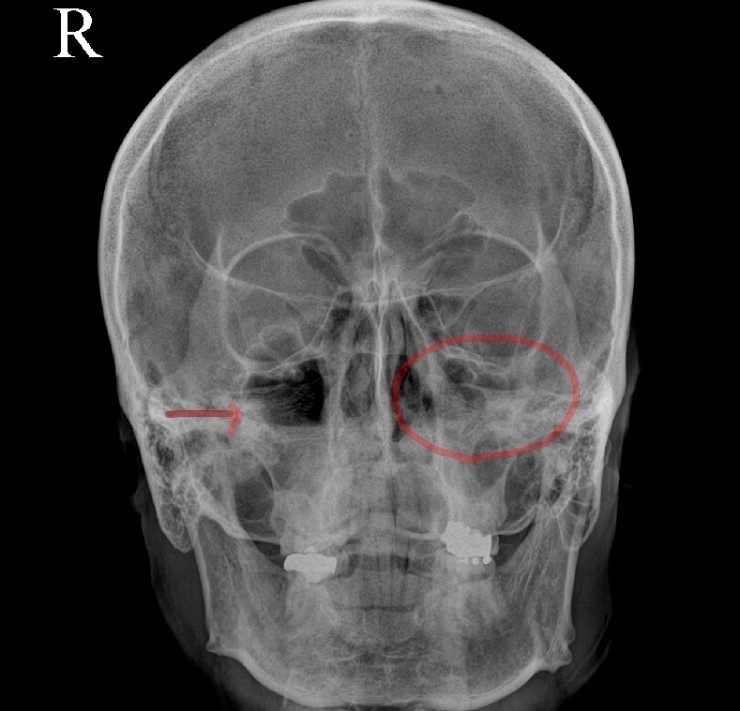

1. 급성 부비동염의 원인은 무엇인가요? ? 1) 급성 비염 – 급성 부비동염의 가장 흔한 원인으로 비점막의 바이러스나 세균 감염이 상악동 점막으로 전이되었을 때 발생 2) 치과 감염 – 충치나 발치로 인한 염증의 확산으로 인한 급성 상악동염3 ) 외상 – 골절 및 안면 외상은 출혈이 축적되어 감염에 취약해질 수 있습니다. 4) 해부학적 폐색 – 해부학, 비강 및 부비동으로 인한 외이구의 환기 및 배액은 할러 낭종, 중격 만곡, 수술 후 유착과 같은 문제를 줄입니다. 5 ) 악안면 기형 – 구개열, 후문 폐쇄증 6) 상기도 감염 – 편도선염, 인두염 및 기타 상기도 감염 7) 전신 상태 – 영양 결핍, 장기간의 스테로이드 치료, 조절되지 않는 당뇨병, 혈액 질환, 화학 요법 등 8) 원발성 섬모 운동 이상증 9) 기타 – 비용 비강 폴립, 이물질, 포장, 오염된 물에서 수영 Johnson & Johnson – 부비동염이란 무엇입니까? 2. 급성 부비동염과 관련된 병원성 박테리아는 무엇입니까? ? 1) 바이러스 – 약 50%의 바이러스에 의해 발생 – Rhinovirus, Parainfluenza, Echovirus, Coxsackievirus, Respiratory Syncytial Virus 등 2) 세균 – Streptococcus pneumoniae, Haemophilus influenzae, Mora catarrh Bacteria 등 칸디다증, 아스페르길루스증 – 전신 쇠약 환자, 당뇨병, 면역억제제 장기 사용 SinusCure – 바이러스성 또는 세균성 부비동 감염? 차이점이 뭐야? 삼. 급성 부비동염의 증상은 무엇인가요? 상안검 부종 및 내안각 압통 – 급성 사골동염 : 비측 및 안구 심부에 통증, 안구를 움직일 때 통증 심화 – 급성 접형동염 : 안구 심부, 후두부, 두정엽, 측두부 통증 2) 누런 가래, 코막힘 – 증상은 1~2주 정도 지속됨 – 콧물은 노란색에서 녹색으로 나타나며 악취가 동반될 수 있음 3) 기침, 가래, 인후통 – 상기도와 유사한 증상 감기에 걸리는 감염 4) 안구주위 증상 – 안구로 인해 부비동염으로 구성되어 있어 안구 주변 부종을 일으킬 수 있음 – 부비동염의 합병증으로 실명에 이를 수 있음 5) 전신증상 – 발열, 권태감, 무기력 등 6) 소아 부비동염 – 아이들은 부비동염의 전형적인 두통을 거의 호소하지 않습니다 – 7일 이상 지속되는 감기와 같은 증상, 밤에 악화되는 기침, 미열 및 콧물 DrJockers.com – 부비동 감염: 원인, 증상 및 자연 지원 전략4. 급성 부비동염은 어떻게 진단됩니까? 부종, 점액, 화농성 분비물에 주의하고 압통 확인 – 인두 검사 중 점액이 인후 뒤쪽으로 흐르는 후비루(PND) 확인 Thumbay Hospital Day Care – 비강 진단에 대해 알아야 할 사항 내시경3 ) 영상진단 (1) 단순방사선검사(X-ray) ① Water view: 상악동이 뚜렷하게 보이는 Radiopaedia – 좌측: 안면골(Waters view), 우측: 급성 상악동염 ② Caldwell view: 사골동이 선명하게 보이는 Radiopaedia – 좌측 : 두개골(Caldwell view), 우: 급성 상악동염 ③ 측면도: 접형동과 전두동이 선명하게 보임 좌: 영상의학과 – 상악동과 안면골(측면), 우: Medscape – 상악동염(sinusitis) 영상화 (2) 상악동의 CT 부비동(PNS CT) – 합병증이 있거나 의심되는 경우, 당뇨나 면역결핍 등의 동반질환이 있는 경우, 약물치료로 증상이 호전되지 않는 경우, 종양이 의심되는 경우, 안면구조에 수술이 필요한 경우 변형되고 비정상적인 부비동 20155년 7월, 치료받은 점막 리슈만편모충증 환자의 다중 검출기 컴퓨터 단층 촬영 스캔. 급성 부비동염 비염) 치료할 수 있습니까? ? 1) 항생제 치료 – 적절한 항생제를 충분한 시간 동안 투여 – amoxicillin 또는 amoxicillin + clavulanic acid Augmentin(augumentin) 5~10일 – macrolide clarithromycin 2차 약제로는 azithromycin 사용 – quinolone계 levofloxacin 또는 ciprofloxacin을 2차로 선 – 2차 선으로 세팔로스포린 사용 – 혐기성 세균이 의심되는 경우 메트로니다졸 또는 클린다마이신 사용* 적절한 항생제 투여로 48~72시간 이내에 임상 증상 호전, 증상 소실 후 최소 3~7일 항생제 투여* 총 권장 치료 기간은 10일에서 3주 이상 위키하우 – 항생제 없이 사는 법 부비동염 없애기 페스티벌: 점막을 수축시켜 부비강의 배액과 환기를 개선하기 위해 사용, 3일 이내 사용 – 항히스타민제: 상기 요인이 있는 경우 사용 가능 알레르기성 비염 – 진통제: 환자의 통증 완화에 사용 – 진정기침 거담제: 부비강의 분비물 배출을 돕는다 3) 상악동 세척 – 상악동 세척으로 상악동 세척으로 치료하여 상악동의 염증성 분비물을 배출하고 환기를 깨끗하게 한다. 감염, 전신 상태 및 해부학적 이상을 바로잡아야 합니다. 5) 수술 – 합병증이 발생하거나 임박한 경우 – 환자가 심한 통증을 호소하거나 적절한 항생제로도 통증이 악화되는 경우 수술을 고려합니다. 코. 위와 매우 유사합니다. . ! 축농증이 의심되는 경우에는 정밀한 신체검사가 필요하기 때문에 최대한 의사에게 알리는 것이 좋습니다! ! 무엇을 하느냐가 차이점 중 하나라고 할 수 있겠네요^^ 긴 글 읽어주셔서 감사하고, 다음 시간에는 “만성 부비동염”에 대해 함께 알아보도록 하겠습니다! 부비동염 = 부비동염 = 비염 + 부비동염 / 급성 부비동염 여러분 안녕하세요! 닥터동동이고 돌아왔습니다! ! 오늘은 흔히 ‘부비동염’이라고 부르는데… blog.naver.com